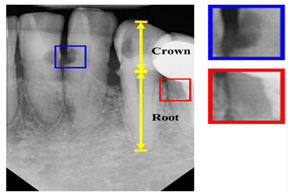

| Periapical X-rays | [12,39,40,59,86,87,88,89,90,91,92,93] | Diagnosing invisible proximal dental caries | ![]() | Display the entire tooth, from the crown to the root, where it connects to the jaw. |